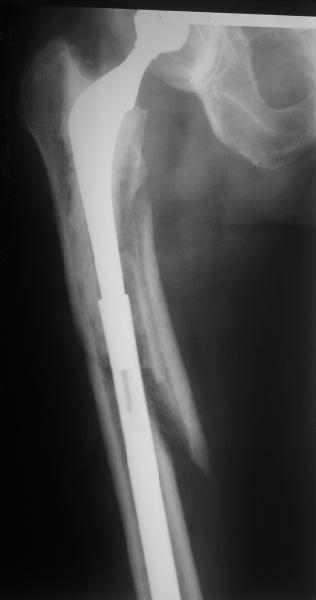

Reminded me of a case I did a couple years ago - 30 year old woman with juvenile rheumatoid arthritis and a nonunion below her stem. Fixed with retrograde nail which docked with the stem and a lateral locking plate. Image attached. One of the companies should come up with a stem design and nail system that anticipates this need.